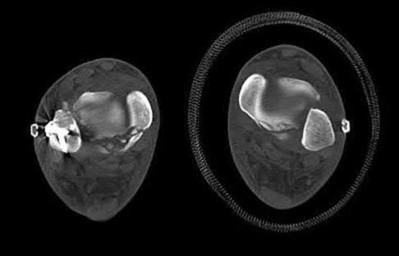

2. # A 35-year-old woman is involved in a head-on collision while driving. Initial radiographs are shown in Figures 8a and 8b. Injury to what vessel increases the risk for osteonecrosis of the injured bone?

5. Artery of the tarsal sinus Corrent answer: 4

The patient has a Hawkins type III talar neck fracture-dislocation with a risk of osteonecrosis ranging from 69% to 100%. Anatomic studies have shown that the artery of the tarsal canal supplies the lateral two thirds of the talar body.

The other vessels listed provide no significant contribution to the talus.